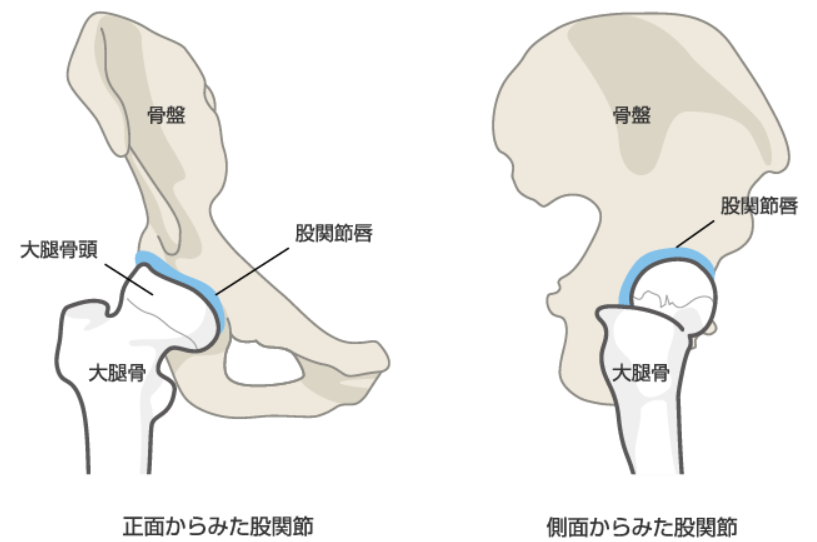

“股関節唇損傷”とは

これまで原因不明とされた股関節痛の中にも、「股関節唇損傷」が含まれていると言われており、現在注目を集めています。股関節唇損傷について説明します。

股関節唇とは、骨盤側の寛骨臼の辺縁を取り巻く柔らかい軟骨で、リング状のゴムパッキンのように大腿骨頭を包み込んでいる部分のことです。 大腿骨頭を安定化させ、衝撃吸収の役割を担っています。 関節唇には神経が存在し、損傷を受けると痛みが生じることがあります。 関節唇損傷が生じると骨頭が安定しなくなり、次第に軟骨が破壊され、変形性股関節症へ移行すると考えられています。

股関節唇損傷の症状

股関節唇が損傷を受けると、脚を動かすような動作に痛みが走ったり、引っ掛かり感を感じたりします。日常生活ではあぐらをかくよう姿勢や、股関節を深く曲げた際、内側へ脚を組むような運動時に痛みや違和感が生じることがあります。靴下を履く、爪を切るなどの股関節を深く曲げるような動作、車の乗り降り、椅子から立ち上がる際に痛みや異常感覚を訴えれば、股関節唇損傷の可能性があります。